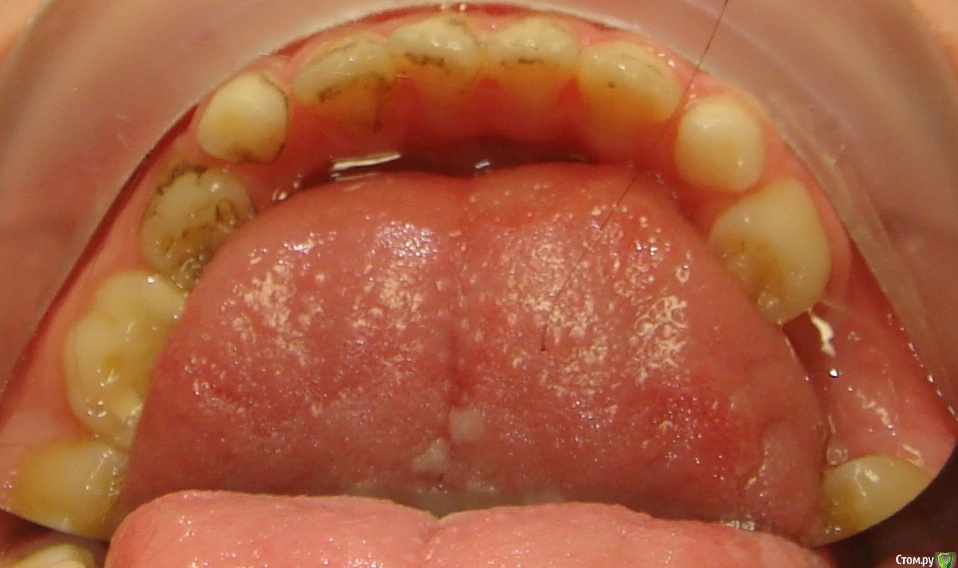

Opdihatop Опубликовано 9 января, 2017 Поделиться Опубликовано 9 января, 2017 Здравствуйте, коллеги! Хотел бы узнать ваше мнение по пациентке. Девочке 7 лет. План лечения в общем мне ясен и понятен. Меня интересует вопрос, когда лучше в данном случае убирать сверхкомплектный премоляр в области 21 зуба, потому что он начал двигать ц.л. вправо. Заранее спасибо! Ссылка на комментарий

Yana guapa Опубликовано 13 января, 2017 Поделиться Опубликовано 13 января, 2017 убрать молочный ц. резец. подождать 6-8 месяцев хотя бы (лучше год) - все ростковые зоны уже значительно выше будут, хирург не задет уже.сделать КТ. и удалить сверхкомплектный. Дать возможность опуститься ц. резцу.сильно долго ждать (до полного формирования корней) не вижу смысла. Очень похожа ситуация была у моей девочки (такое же расположение). - очень долго не хотел ц. резец спускаться. Райц-терапия в помощь)) вышел)) Ссылка на комментарий

Yana guapa Опубликовано 16 января, 2017 Поделиться Опубликовано 16 января, 2017 21? 61 . и 62 можно, у него все равно корень рассосался уже )) Ссылка на комментарий